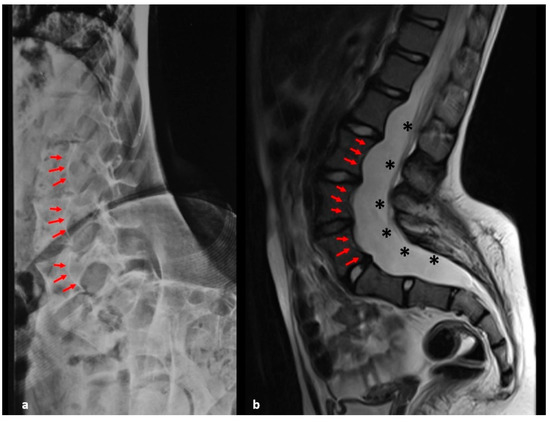

| Vertebral Dystrophic Changes |

|---|

| Vertebral Scalloping (present when the depth of scalloping is >3 mm in the thoracic spine or >4 mm in the lumbar spine) |

| Rib penciling (rib width lower than the narrowest portion of the second rib) |

| Spindling of the transverse processes (loss of 50% from the height of the transverse process measured in the middle point between the lateral edge of the vertebral body and tip of the transverse process and compared with the contralateral normal side or uninvolved vertebra above or below) |

| Focal, short-segmented curve (involving 6 or less vertebrae) |

| Dural ectasia |

| Paraspinal tumors or plexiform neurofibromas close to the scoliosis curve |

| Vertebral wedging |

| Intervertebral foraminal widening |

| Widened interpediculate distances |

| Dysplastic pedicles |